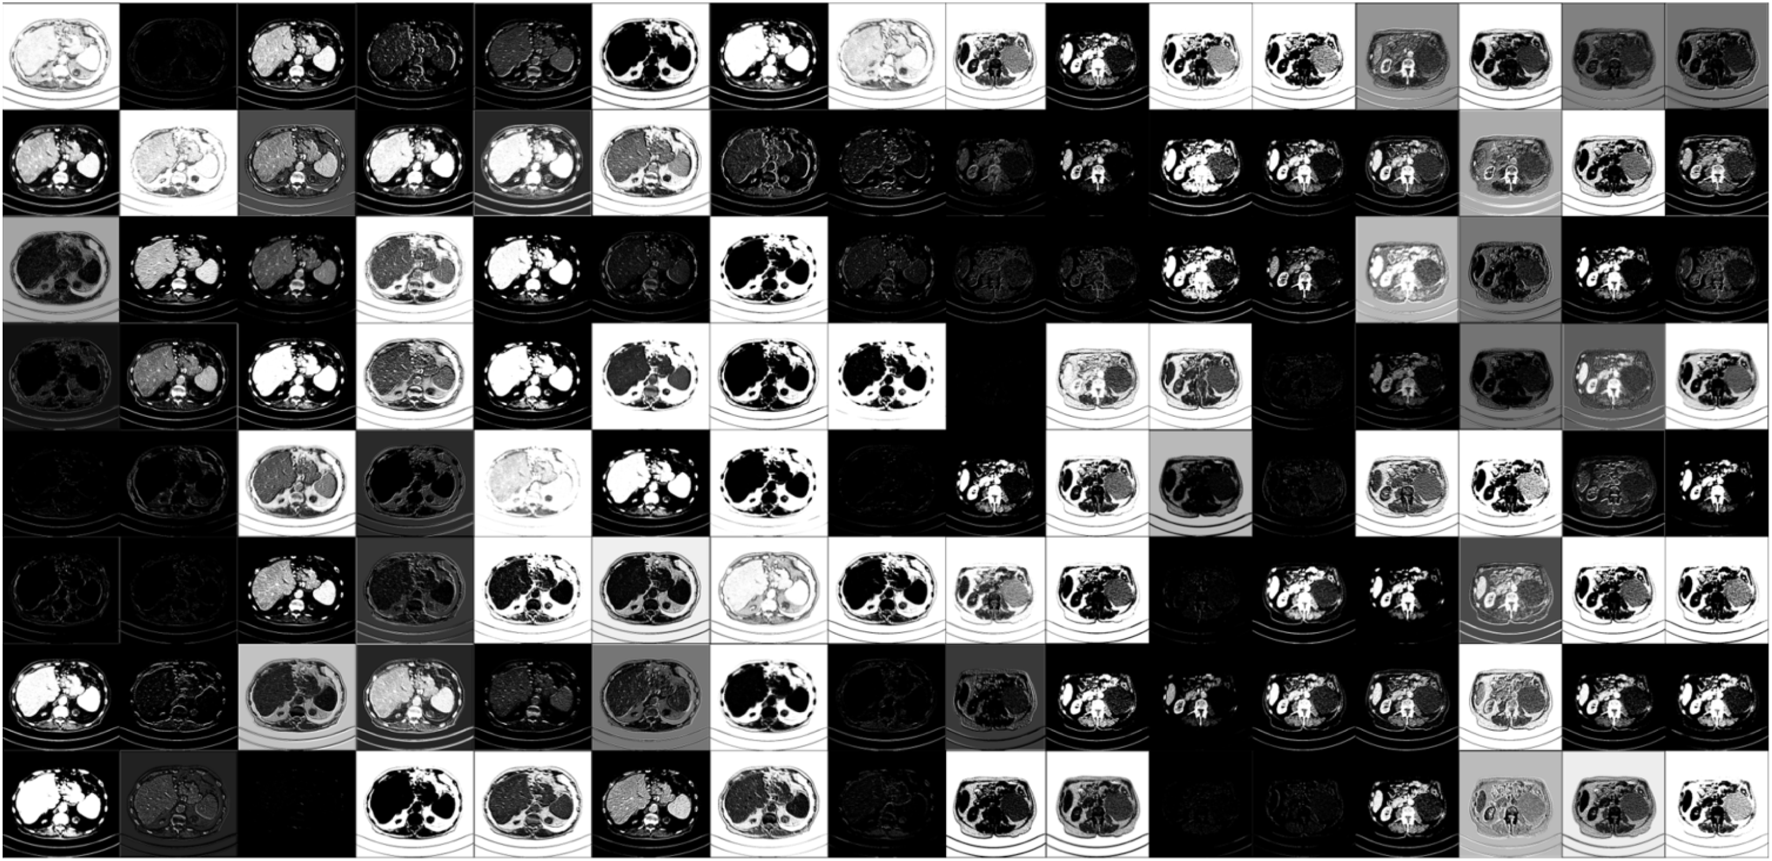

For visualizing and understanding the internal working mechanism of our proposed DRBNet, Figure 8 shows feature maps from our model once the training is finished. Modules in DRBNet performing CT image feature extraction is significant for tasks of LDCT image denoising. The Feature maps shown in Figure 8 are organized into an array with size of 8 × 16. Each small sub-image emphasizes the features of the original CT images, i. e., whole structures, edges, and boundaries. Thus, we believe that the proposed DRBNet can fully learn the features of CT images and can fully demonstrate its capabilities in the tasks of low-dose CT image denoising.

Figure 8. Visualization of feature maps of CT images extracted from different layers in our proposed trained DRBNet.